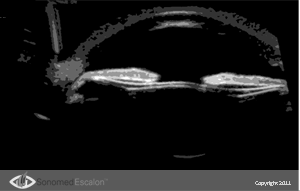

При послеоперационной диагностике VuMAX® позволяет хирургу наглядно представить позицию ИОЛ и ее взаимодействие с различными структурами переднего отрезка. Появление имплантируемых контактных линз (?КЛ), ставшее очень хорошей альтернативой для некоторых пациентов, дает превосходные результаты при правильном их расположении. VuMAX® обеспечивает точные и правильные измерения “борозда – борозда” и/или “угол – угол” (в зависимости от типа имплантируемой ?КЛ).

Сделать точные и правильные измерения очень легко. Нужно лишь предварительно выбрать кадр с правильно ориентированным изображением. Возможность записывать процедуру сканирования в форме видео клипа (со скоростью 22 кадра/сек), а затем просмотреть каждый кадр в отдельности, поможет хирургу подобрать кадр с правильно ориентированным изображением.

При послеоперационной диагностике с помощью VuMAX® хирург может получить ряд очень важных данных, которые недоступны без использования высокочастотной ультразвуковой биомикроскопии. Совершенно четко на эхограмме можно проследить следующие параметры: правильно ли расположены опорные элементы линзы, расположена ли она по центру и нет ли контакта имплантированной линзы с нежелательными структурами.